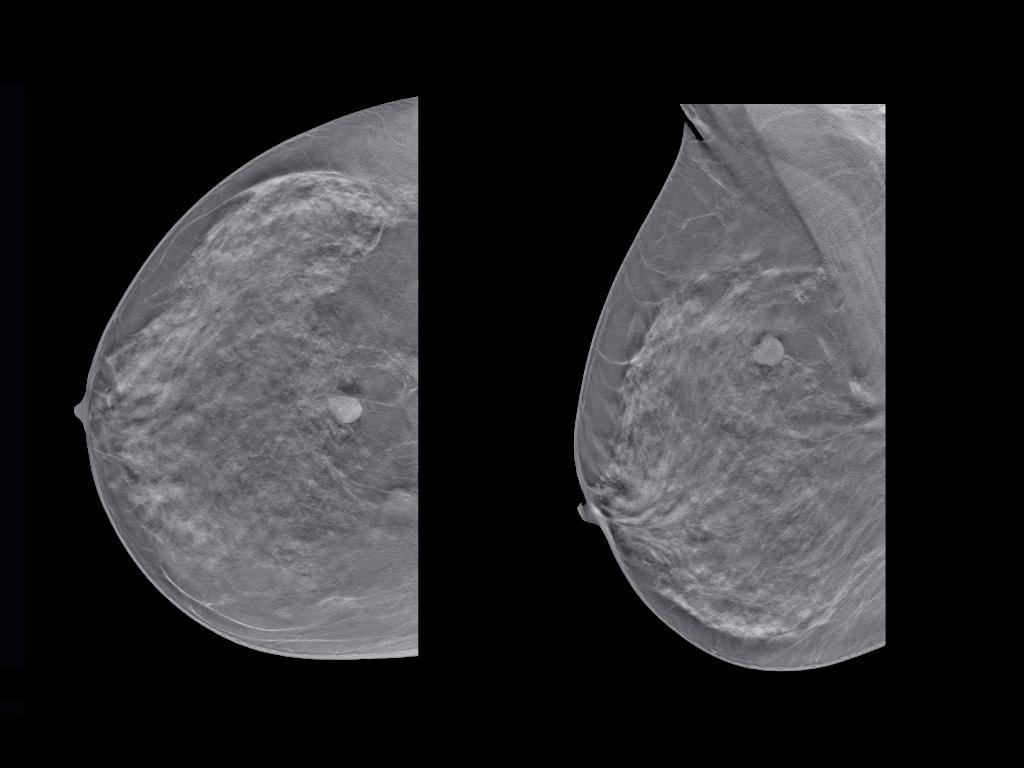

De cualquier manera, la mamografía es el método más eficaz para este fin. De acuerdo con la Sociedad Alemana contra el Cáncer (Brustkrebs Deutschland e.V) el tamaño medio de un bulto detectado por mamografía es de 0,5 cm, mientras que el tamaño medio de un bulto que las mujeres pueden detectar mediante la autoexploración habitual es de 2 cm.